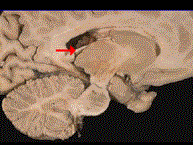

如图箭头所示为大脑哪个部位 ( )A、穹窿B、中脑导水管C、透明隔D、室间孔E、前连合

问题 如图箭头所示为大脑哪个部位 ( )

选项 A、穹窿 B、中脑导水管 C、透明隔 D、室间孔 E、前连合

答案 A